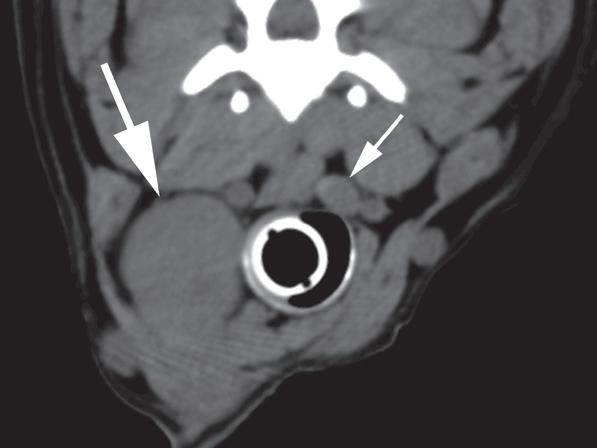

Rycina 1.11.6. Rak tarczycy i gruczolak tarczycy (pies) TK

Badanie wykonano u 12-letniej, kastrowanej samicy owczarka australijskiego z prawostronną masą w dobrzusznej części szyi. Badanie USG wykazało dużą, litą, unaczynioną masę w obrębie prawego płata tarczycy (a) oraz mniejszą, hipoechogeniczną masę w obrębie lewego płata (b). Obrazy TK przed i po podaniu środka kontrastowego (c–f) ułożone od doczaszkowych do doogonowych ukazują dużą, prawostronną, jednorodnie wzmacniającą się masę (c–f – duża strzałka) z niewyraźną granicą dobrzuszną oraz pozatorebkowym szerzeniem się i rozlanym wzmocnieniem pokontrastowym przyległych tkanek (e, f – grot strzałki). W obrazie bardziej doczaszkowym widoczny jest prawidłowy lewy płat (c, e – mała strzałka), natomiast w obrazie bardziej doogonowym jest on powiększony i ma niższą gęstość, niż można by oczekiwać, co sugeruje obecność drugiej, mniejszej masy (d, f – mała strzałka). W obrazach reformowanych wzdłuż osi długiej widać dwa małe guzki w lewym płacie (h – małe strzałki). Wyniki obrazowe potwierdzono podczas zabiegu (i, j – strzałki). Biopsja wycinkowa wykazała prawostronnego raka tarczycy z naciekaniem pozatorebkowym oraz lewostronnego gruczolaka tarczycy